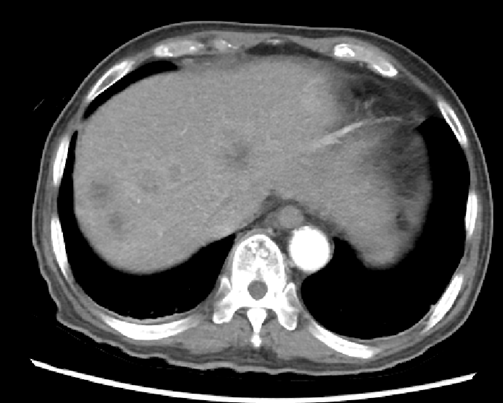

2019.11.18 腹部CT:肝脏多发结节(图2),考虑转移。

图2. 腹部CT(2019.11.18)